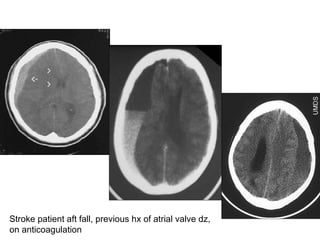

Stroke patient aft fall, previous hx of atrial valve dz, on anticoagulation

CT- subdural hemorrhage Describe? Hyperdense crescent-shaped hematoma Midline shift Compress ventricle Dx? Subdural hemorrhage Causes? Head injury (venous rupture) Risk factor? Elderly Alcoholic (accident prone + atrophic brain) Anticoagulant  S&S? Headache, drowsy, confusion (fluctuate) Long latent interval btw injury & symptoms

Stroke patient aftfall, previous hx of atrial valve dz, on anticoagulation

CT- subdural hemorrhageDescribe? Hyperdense crescent-shaped hematoma Midline shift Compress ventricle Dx? Subdural hemorrhage Causes? Head injury (venous rupture) Risk factor? Elderly Alcoholic (accident prone + atrophic brain) Anticoagulant S&S? Headache, drowsy, confusion (fluctuate) Long latent interval btw injury & symptoms